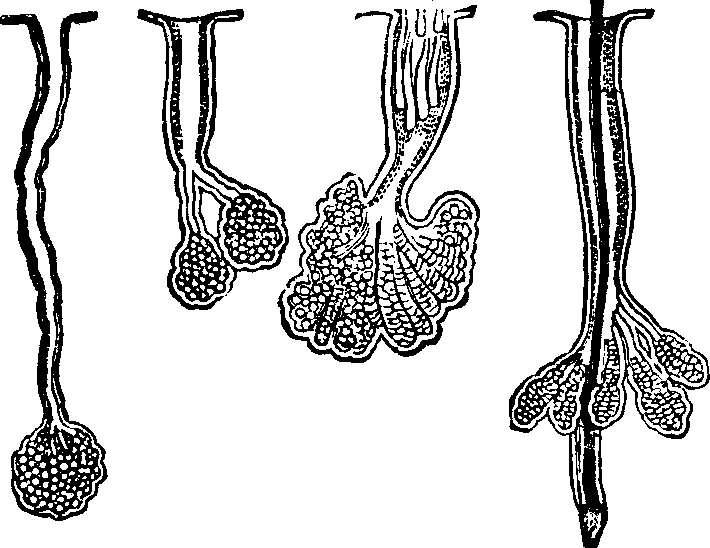

Fig. 35. Villi of the small

intestine greatly magnified.

Absorption is the vital function by which nutritive materials are

selected and imbibed for the sustenance of the body. Absorption, like all

other functional processes, employs agents to effect its purposes, and the

villi of the small intestine, with their numberless projecting

organs, are specially employed to imbibe fluid substances; this they do

with a celerity commensurate to the importance and extent of their duties.

They are little vascular prominences of the mucous membrane, arising from

the interior surface of the small intestine. Each villus has two sets of

vessels. (1.) The blood-vessels, which, by their frequent blending, form a

complete net-work beneath the external epithelium; they unite at the base

of the villus, forming a minute vein, which is one of the sources of the

portal vein. (2.) In the center of the villus is another vessel, with

thinner and more transparent walls, which is the commencement of a

lacteal.

Fig. 36. A general view of the

Lymphatic System.

Fig. 37. 1. A

representation of a lymphatic vessel highly magnified. 2. Lymphatic valves.

3. A lymphatic gland and its vessels.